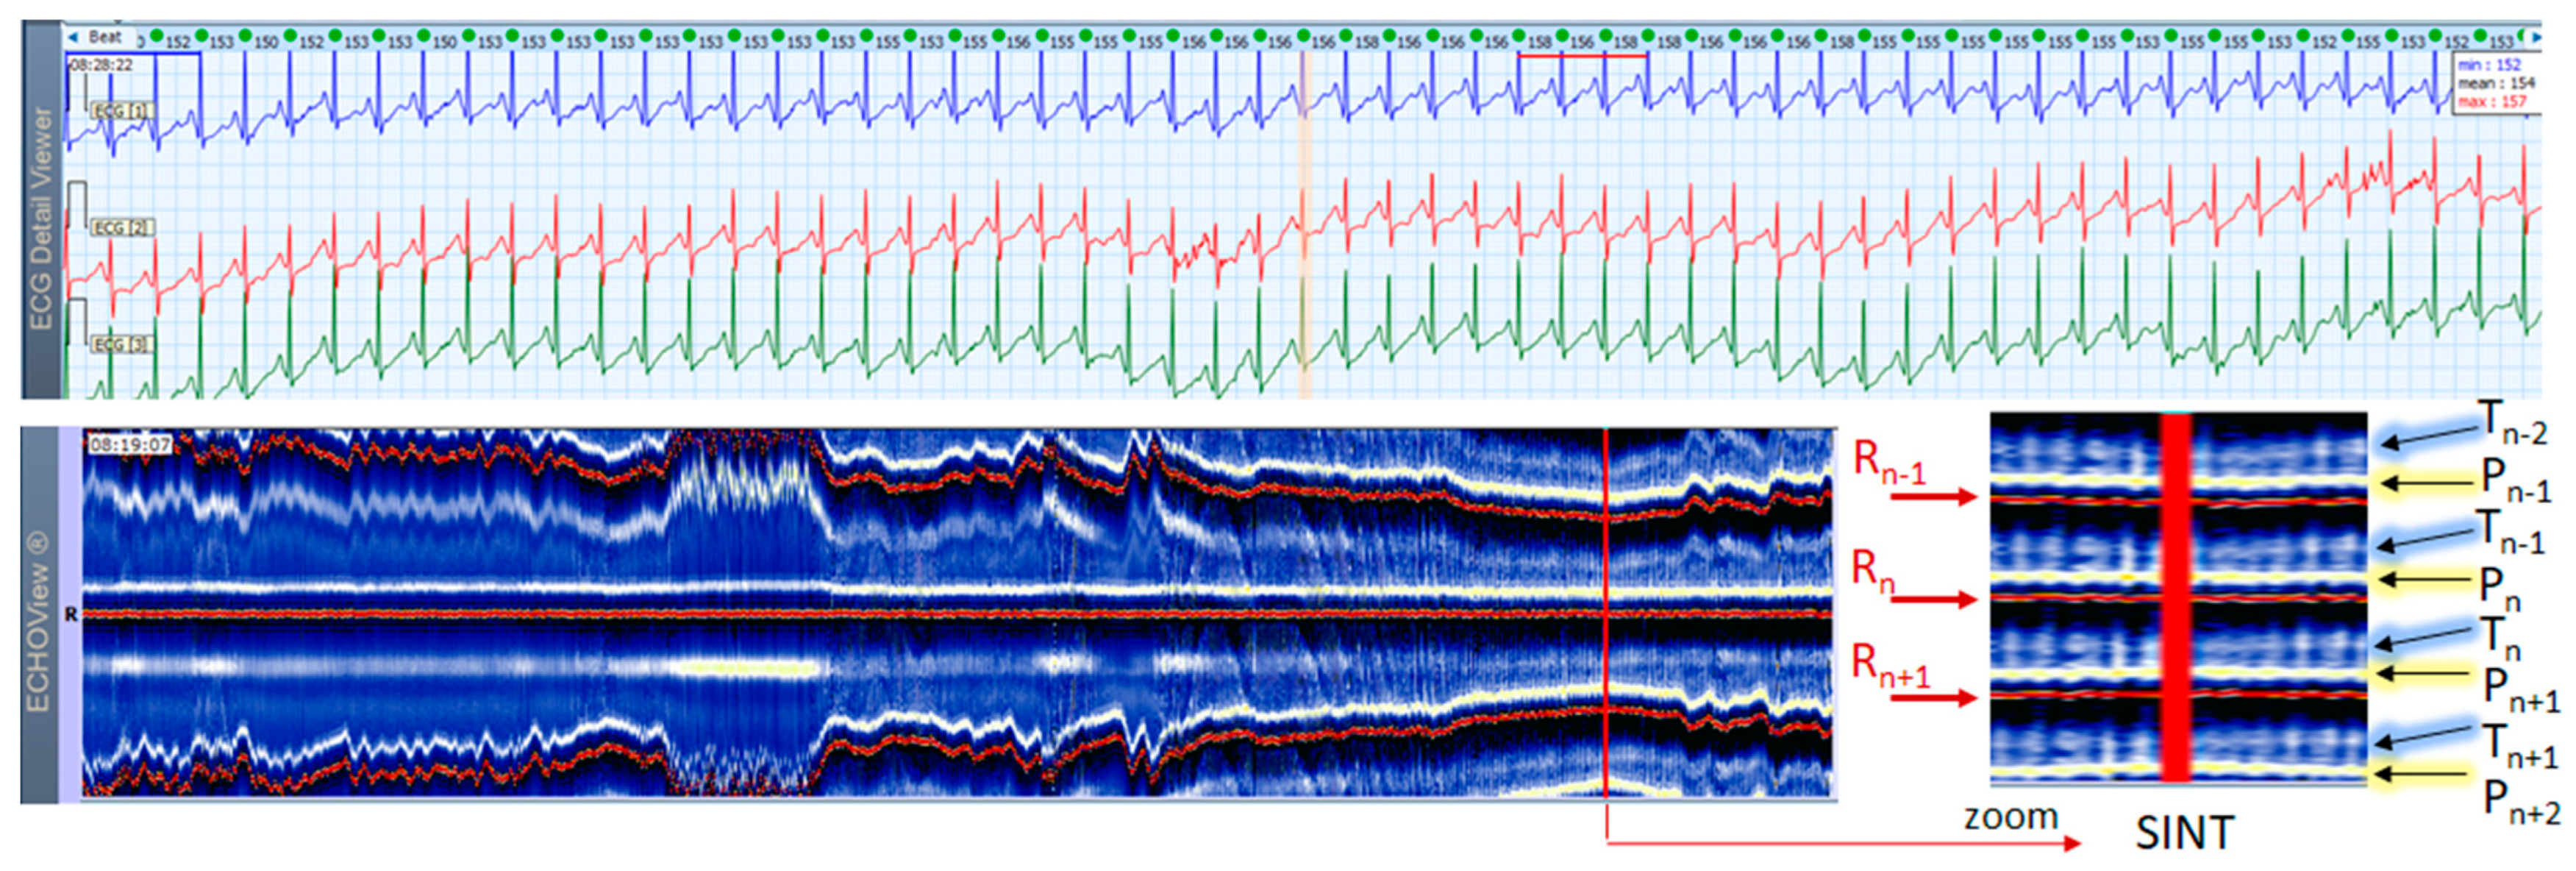

3.3. Sinus Tachycardia Cases

This section interprets together 3-lead Holter ECG strips and the corresponding ECHOView images (ECG lead 1) of three patients with SINT (Figure 6, Figure 7 and Figure 8). When the HR is too high, it is sometimes difficult to differentiate true SINT, caused by a physiological increase in the sinoatrial node activity from SVTs due to re-entry circuits, increased focal atrial automaticity, or triggered activity. The examples below represent somewhat complex cases from an ECG diagnostic perspective, where SINT mimics atrioventricular reentrant tachycardia (AVRT) (Figure 6), or focal atrial tachycardia, atrioventricular nodal reentrant tachycardia (AVRNT) (Figure 8), AFL with AV conduction 2:1 (Figure 6 and Figure 8) or atrial tachycardia (Figure 7). The general difficulty is the recognition of the sinus P-wave at high cardiac rates, particularly in Holter ECG strips recorded with less number of channels than the standard 12-lead ECG (usually made at rest, when sinus tachycardia is not so common). As shown in one-lead ECHOView images below, the sinus P-wave band in SINT is well seen as a blue-white band. In the three examples, it maintains a constant distance from the red band of the central R-peak, which stands for a stable PR-interval, regardless of beat-by-beat RR-interval change. The latter is well seen in the ECHOView images by three horizontal red traces for three sequential R-peaks, presenting useful information on the long-term HR variation in SINT, which demonstrates patient-specific dynamics in the three examples.

ECHOView interpretation turned out to be very important for some of our patients with episodes of supraventricular rhythm disorders such as SINT, SVT, AF and AFL. These arrhythmias are very common among the general population, affecting both younger and older people, with or without underlying cardiac injury [1,2,3,4,5,6,7]. A lot of non-cardiac conditions such as thyroid dysfunction, chronic lung diseases, electrolyte disturbances, infections (including COVID-19), etc. could also ‘unlock’ SVAs [1,2,8]. The diagnosis is based mostly on non-invasive ECG methods, mainly standard 12-lead ECG and 24–72 h Holter ECG monitoring [1,2,3,4,5,6,7,8,9,10]. Standard 12-lead ECG records are obtained in rest and their quality is usually much better than Holter ECG records, but conventional ECGs are not the ideal tool for diagnosing arrhythmias. They present time frames of about 10–20 s and many patients with SVAs could be missed because arrhythmias are often transitory [1,2,3,4,5,8]. For this reason, diagnosis is usually obtained by Holter ECG monitoring or event recorders [1,2,3]. However, most of these devices record less number of channels (1 to 3) in which P-waves of the normal sinus rhythm may not be demonstrated [1,2,3,4,5,6]. In addition, external factors such as movements, posture, skin contact of the electrodes, etc. may exert significant influence on the quality of the records and the morphology of ECG components, thus making the detection of P-waves even more difficult [1,8,17]. One of the most common ECG challenges is the differentiation of a high-rate sinus tachycardia from other SVTs (AVNRT, AVRT, focal AT) and sometimes from high-rate AF/AFL. Physical activities, emotions, panic attacks, pain/severe discomfort, febrility, etc. may cause expressed sinus tachycardia with complaints indistinguishable from a true tachyarrhythmia [3,5,9]. The ECG leads to shortening of the RR intervals, the impossibility of recognizing regularity/irregularity of the rhythm, and identifying/distinguishing the normal sinus P-wave from pathological P-waves of AT, F waves of AFL and f-waves of AF could make diagnosis uncertain, particularly if the patient has already had arrhythmias or risk factors for the development of them [5,7,9]. In this article we present several cases in which patient’s complaints and the Holter ECG records required differentiation between SINT, SVT and AF/AFL. In our cases, ECHOView facilitated the accurate diagnosis clearly disclosing the P-wave in SINT (Figure 6, Figure 7 and Figure 8) and the pathological atrial excitations in cases of true tachyarrhythmias SVT (Figure 10, Figure 11, Figure 12 and Figure 16), AF (Figure 13, Figure 14 and Figure 16) and AFL (Figure 15 and Figure 16) but also the contrastive ventricular pattern of NSVT. As the prognostic significance and therapeutic approach to arrhythmias can vary greatly [40], such as the need for oral anticoagulation in AF/AFL [1,2], the advanced perspective of ECHOView is an important tool to improve risk assessment and therapeutic decision-making.

4.3. ECHOView: Summary of the Principles of Imaging

The color-coded ECG amplitudes of sequential beats produce an intuitive trace of different intervals (PnRn, RnTn, Rn−1Rn, RnRn+1, etc.) in a visible image (width × height = 1740 beats × 1500 ms) within one ECHOView page. Without a specific measurement, this visual effect resembles the rendering of one-dimensional time trends of automatically measured ECG intervals. These trends show stable PnRn and RnTn intervals during the NSR part of the examples in Figure 4, Figure 5, Figure 6, Figure 7, Figure 8, Figure 9, Figure 10, Figure 11 and Figure 12. The trends are also informative for the RR-intervals (Rn−1Rn, RnRn+1) on a beat-by-beat basis that is helpful for identifying long-term HR changes in high-rate SINT (Figure 6, Figure 7 and Figure 8) and AFL (Figure 15), as well as rhythm, transitions NSR→ paroxysmal SVA (Figure 9), NSR→PSVT (Figure 10, Figure 11 and Figure 12), NSR→NSVT (Figure 10, Figure 11 and Figure 12), and AF→AFL→ST (Figure 16).

Figure 7. A 3-lead Holter ECG strip (22 s, 25 mm/s) and ECHOView image (ECG lead 1, height = 1500 ms, width resolution = 80 beats/25 mm) of a 21-year old female patient with SINT. The two pages (ECG—top and ECHOView—bottom) are aligned with vertical lines in the highest rate SINT (max HR = 158 bpm read from instant HR values above each QRS complex in the ECG page). In ECG, the atypical morphology of the P-wave (narrow-based, tall, and sharp) and its superimposition on the previous T-wave requires differentiation from an atrial tachycardia. In ECHOView (original and zoomed), the P-wave is a visible blue-white horizontal band (Pn), preceding the red R-wave line (Rn), which confirms the sinus rhythm. ECHOView color map: Yellow-white trace (P-wave of the atrial depolarization, Pn: current, Pn+1, Pn+2: 2 next, Pn−1: previous); Red traces (R-peak of ventricular depolarization, Rn: current, Rn+1: next, Rn−1: previous); Blue-white traces (T-wave of ventricular repolarization, Tn: current, Tn+1: next, Tn−1, Tn−2: 2 previous). SINT—sinus tachycardia.